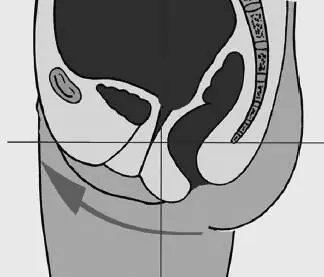

Рис. 77. Отклонение таза назад, крестец опущен

Все отклонения положения таза либо спазмируют мышцы тазового дна, либо, напротив, перерастягивают, в результате чего они провисают растянутым гамаком.